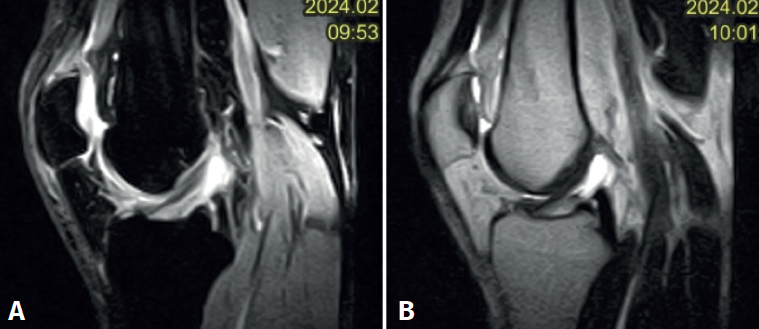

Figura 3. Visión artroscópica desde el portal anterolateral de la rodilla derecha. Se observa el quiste sinovial del ligamento cruzado anterior (LCA) en el fascículo posterolateral. A: visión con palpador diferenciando fibras del LCA sano del quiste; B: visión con la rodilla en posición “de cuatro” en la que se observa el pinzamiento del quiste en el espacio tibiofemoral lateral.

En ambos pacientes se realizó anestesia raquídea para realizar la cirugía y se utilizó manguito de isquemia a nivel del muslo. Se colocó al paciente en decúbito supino, utilizando un soporte en U en el tercio distal del muslo para la fijación de la extremidad. Se realizaron los portales artroscópicos habituales anterolateral y anteromedial, objetivando en la exploración diagnóstica de la rodilla la presencia de un ganglión localizado en el fascículo posterolateral del LCA (Figura 3) que, cuando se realizaban los movimientos de flexión y en posición de cuatro, se pinzaba en el espacio articular tibiofemoral externo. Para realizar la resección artroscópica del quiste se colocó al paciente en la posición “de cuatro”, facilitando la diferenciación anatómica de los fascículos anteromedial y posterolateral del LCA, tal y como proponen Hopper G et al.(4). Se realizó la disección y exéresis cuidadosa del quiste con una pinza basket, un terminal shaver de 4 mm y un terminal de ablación por radiofrecuencia (Figura 4). Al finalizar la resección del quiste, se realizó una nueva exploración dinámica de la rodilla, donde se evidenció la ausencia de pinzamiento entre el LCA, el cóndilo femoral y el platillo tibial lateral, a la vez que se comprobó la estabilidad del remanente del LCA (Figura 5).